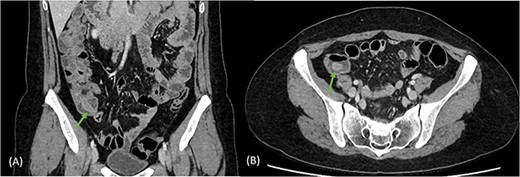

A 41-year-old female presented to the emergency department with a 6-day history of nausea, diarrhoea, per rectal (PR) bleeding on straining, and generalized abdominal pain that was most prominent in the right iliac fossa (RIF). This is on the background of a previous similar episode 4 months ago which self-resolved after 3 days. Past medical history was significant for previous left oophorectomy via a right paramedian incision performed overseas and laparoscopic cholecystectomy. She had no reported history of appendicectomy. There was no history of allergies or other atopic skin conditions. On examination, the abdomen was soft and tender in the RIF without guarding or peritonism. Full blood count and biochemistry were unremarkable. Contrast enhanced CT of the abdomen and pelvis demonstrated a tubular rim enhancing structure in the caecal lumen with surrounding fluid, which was suspicious for invaginated appendix that was otherwise not identified (Fig. 1). She was conservatively managed with intravenous antibiotics and discharged home with oral antibiotics after 3 days. Outpatient colonoscopy performed 10 days postdischarge demonstrated a visible invaginated appendix within the caecal pole (Fig. 2). No other mucosal lesions or abnormalities were identified. On outpatient review, the patient reported ongoing right-sided abdominal pain without further PR bleeding and proceeded to a laparoscopic stapled caecectomy 4 days later. Intraoperatively, there were adhesions to the previous right paramedian incision. The appendix was within the caecum and appeared to have been tied there with suture material at the base (Fig. 3). Histopathology showed an appendix with eosinophilic granulomas and there was no evidence of helminth infection. The patient had an uneventful postoperative recovery process and was discharged home on Day 2 postoperation. She was well upon reviewed in the outpatient clinic 1 month later and was discharged.

Coronal (A) and axial (B) views of CT scan demonstrating tubular rim enhancing structure in the caecal lumen with surrounding fluid, suspicious for invaginated appendix, which was otherwise not identified.